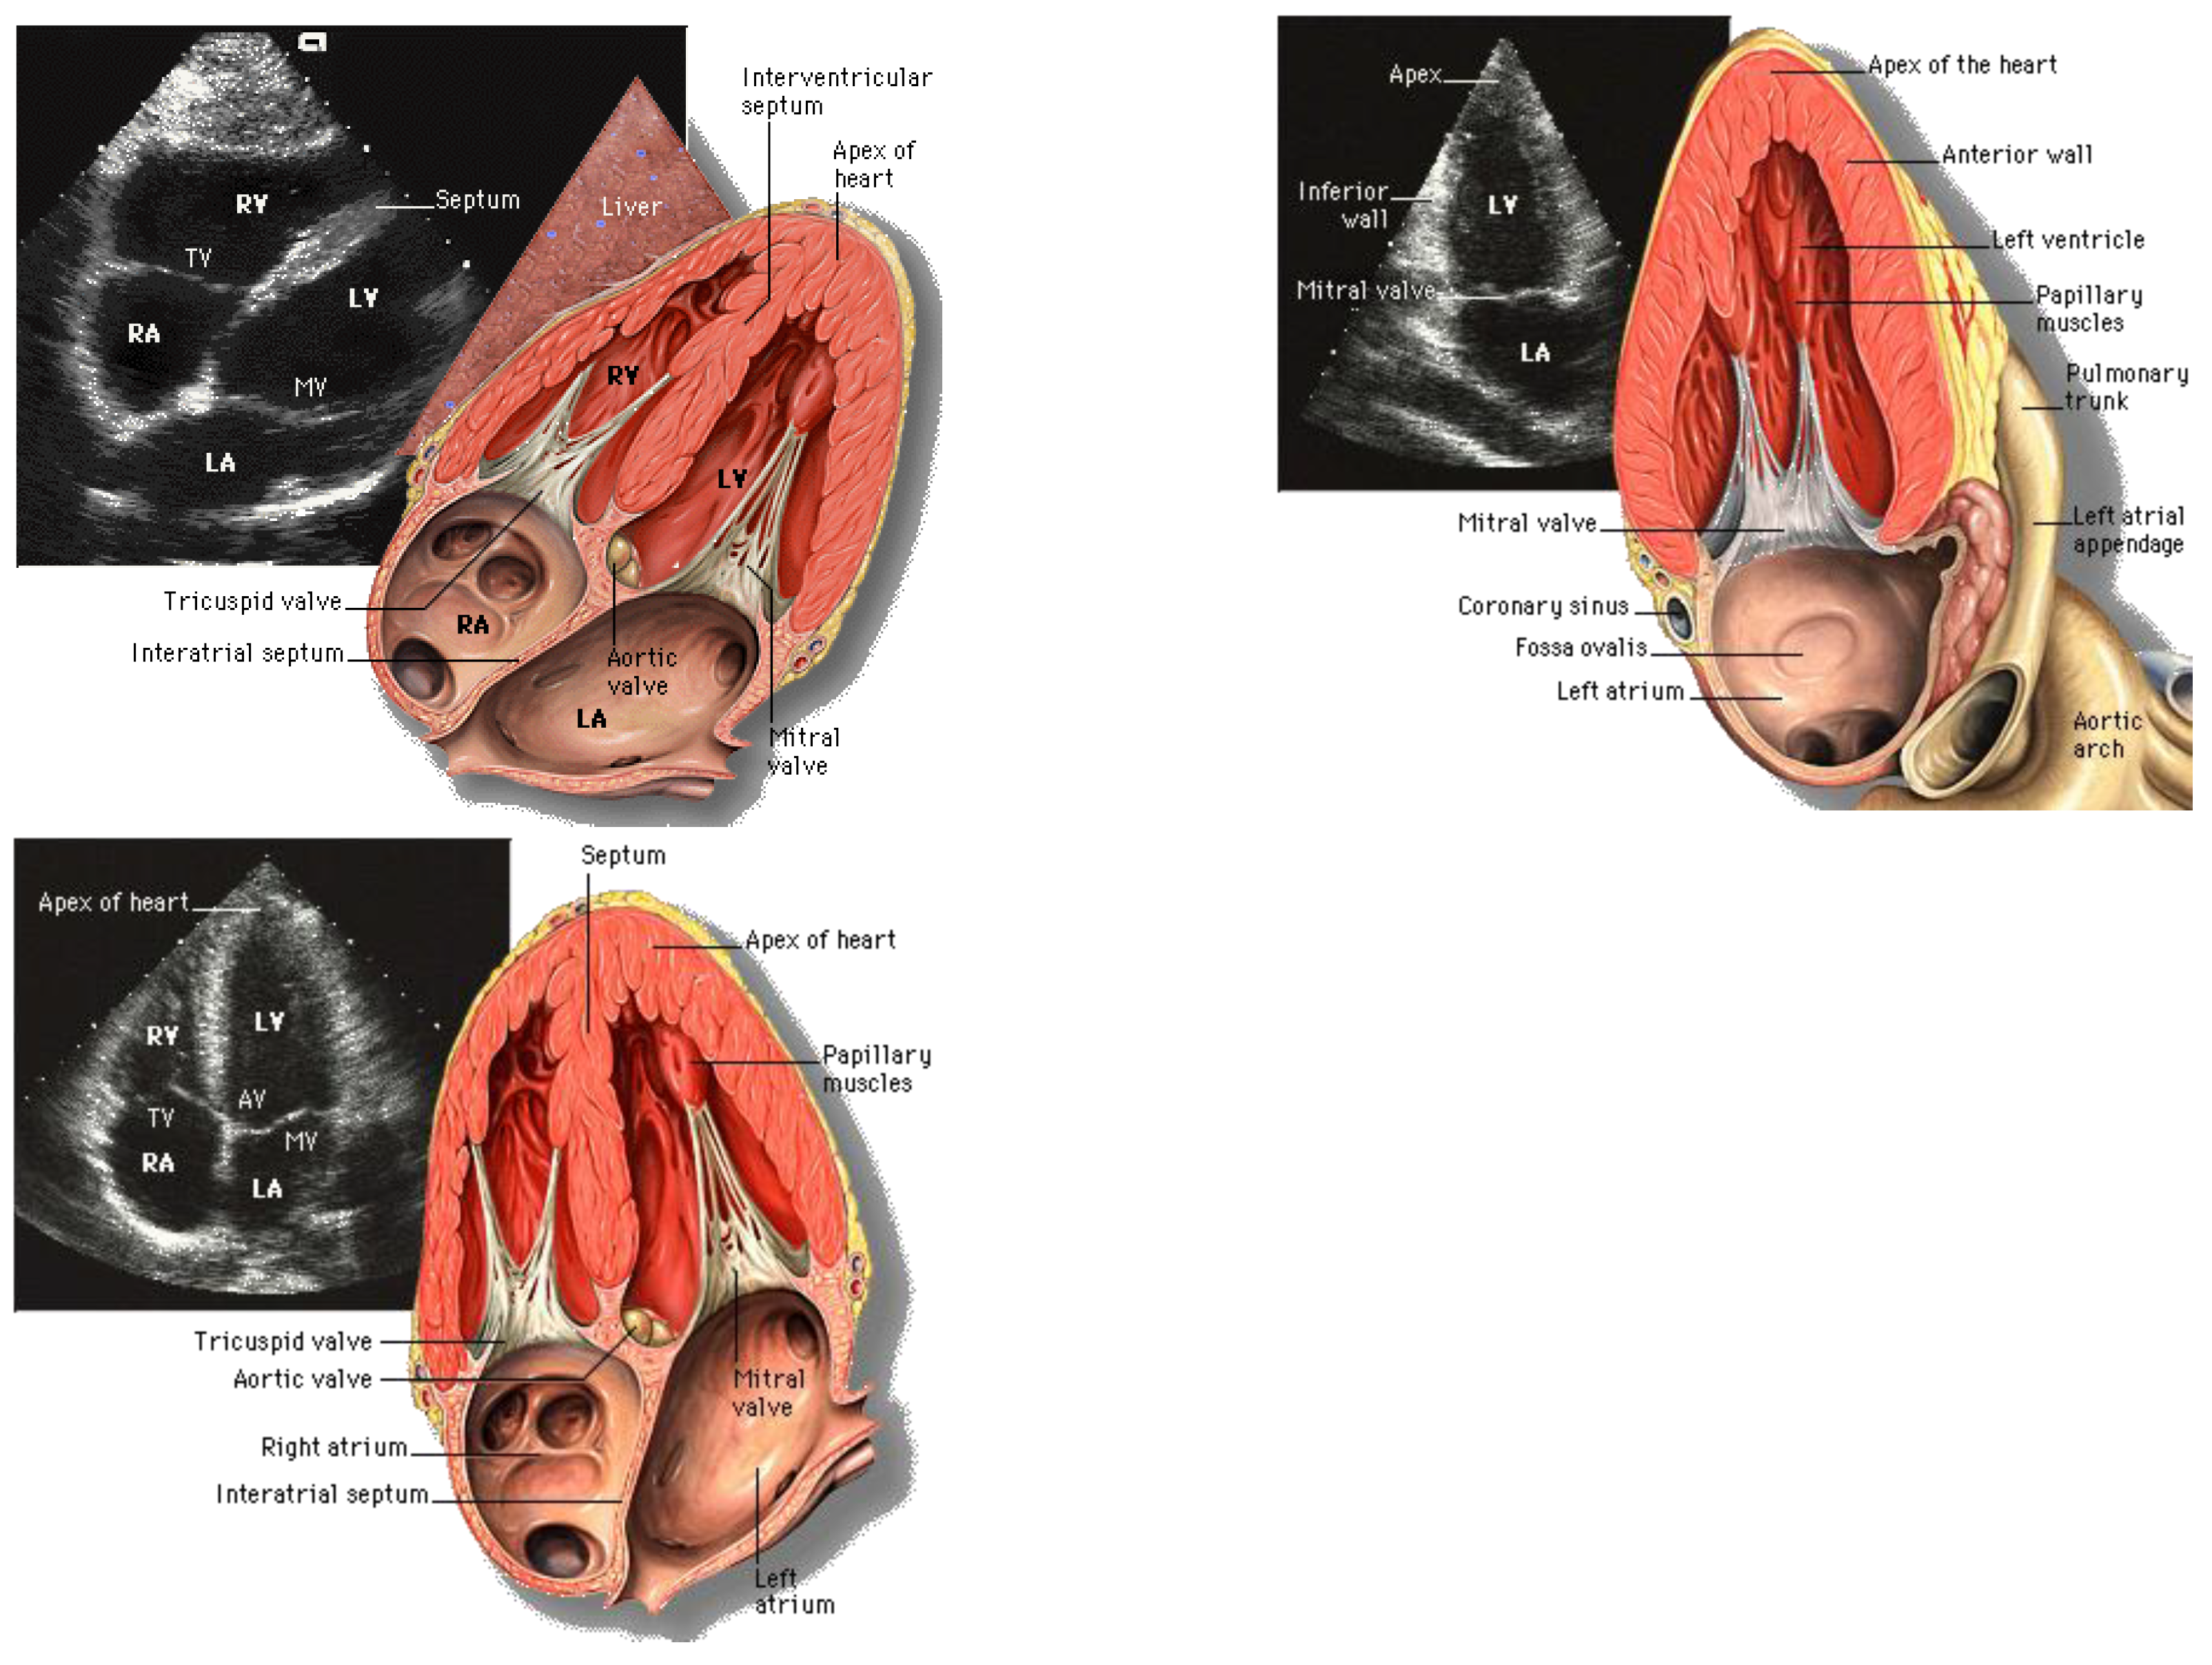

4.4. Echocardiography or Ultrasound (US)

4.4.1. Imaging Techniques

- Standard Transthoracic Echocardiogram: Complete Imaging Protocol. Cardiovascular Education. Available online: https://ecgwaves.com/topic/the-standard-adult-transthoracic-echocardiogram-a-protocol-to-obtain-a-complete-study/ (accessed on 8 July 2024).

- My medical illustrations. Patrick Lynch. January 22, 2017. Available online: https://coastfieldguides.com/my-medical-illustrations/ (accessed on 8 July 2024).

- Chen, C.; Qin, C.; Qiu, H.; et al. Deep Learning for Cardiac Image Segmentation: A Review. Front Cardiovasc Med. 2020, 7. [Google Scholar] [CrossRef]